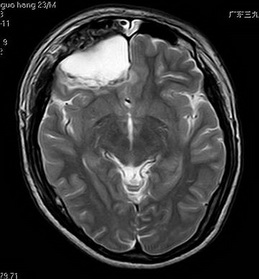

之后,钟先生来到广东三九脑科医院,头部MRI提示:右侧额叶软化灶形成并胶质增生;双侧基底节区小软化灶、胼胝体异常信号影,考虑陈旧轴索损伤可能;幕上弥漫性脑皮质萎缩。癫痫内科医生建议其手术治疗,但因经济条件等原因,钟先生继续服药治疗了几年。

最近1个月以来,钟先生的发作变得频繁,1个月发作2次。他来到神经外六科进一步检查,视频脑电图显示:重度异常脑电图;右侧颞区见少量中高波幅棘-慢波发放。脑磁图提示:右额区见稍多棘波发放。颅脑MR提示:右侧额叶软化灶形成并胶质增生;双侧基底节区小软化灶、胼胝体异常信号影,考虑陈旧轴索损伤可能;幕上弥漫性脑皮质萎缩。

术前MR